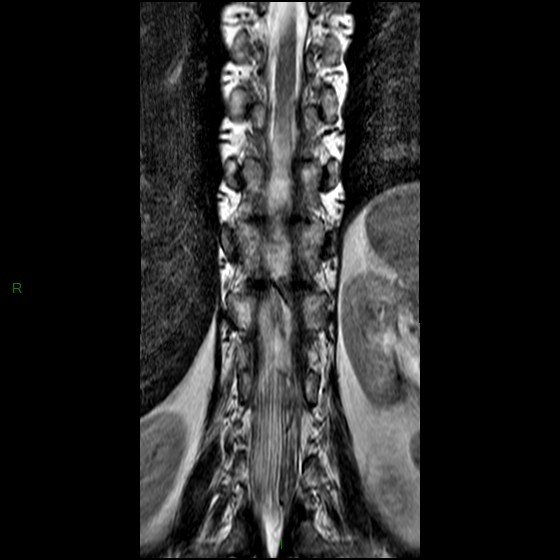

• Fistule durale lombaire